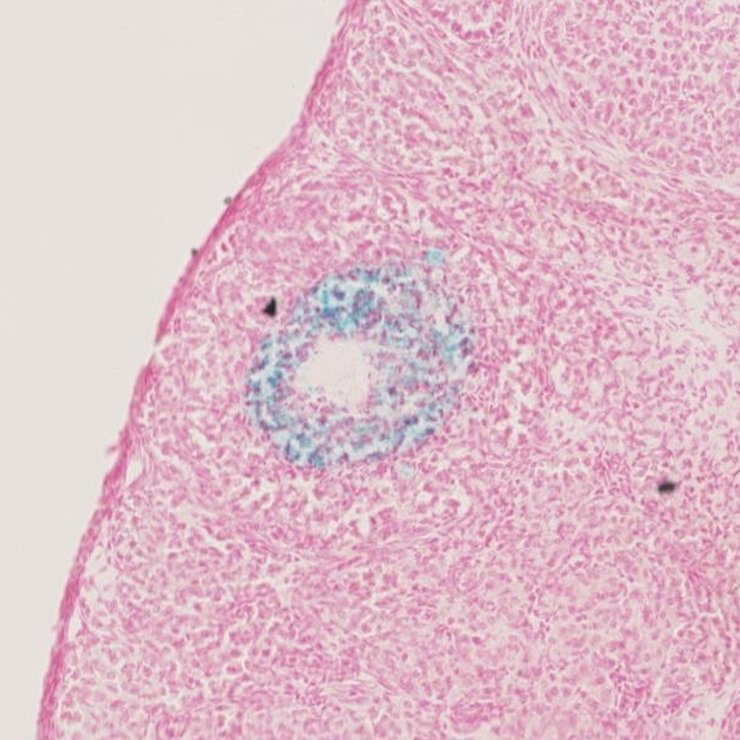

TS28: ovary Present JAX_1279481

Specimen JAX_1279481: postnatal adult; Tex101tm1b(KOMP)Wtsi/Tex101+ (more )